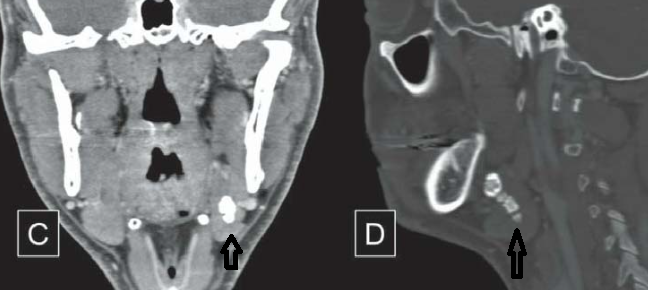

Compression du Wharton par un volumineux calcul (halo de salive en hyperT2), dilatation des canaux submandibulaire

Calcul salivaire sialadénite